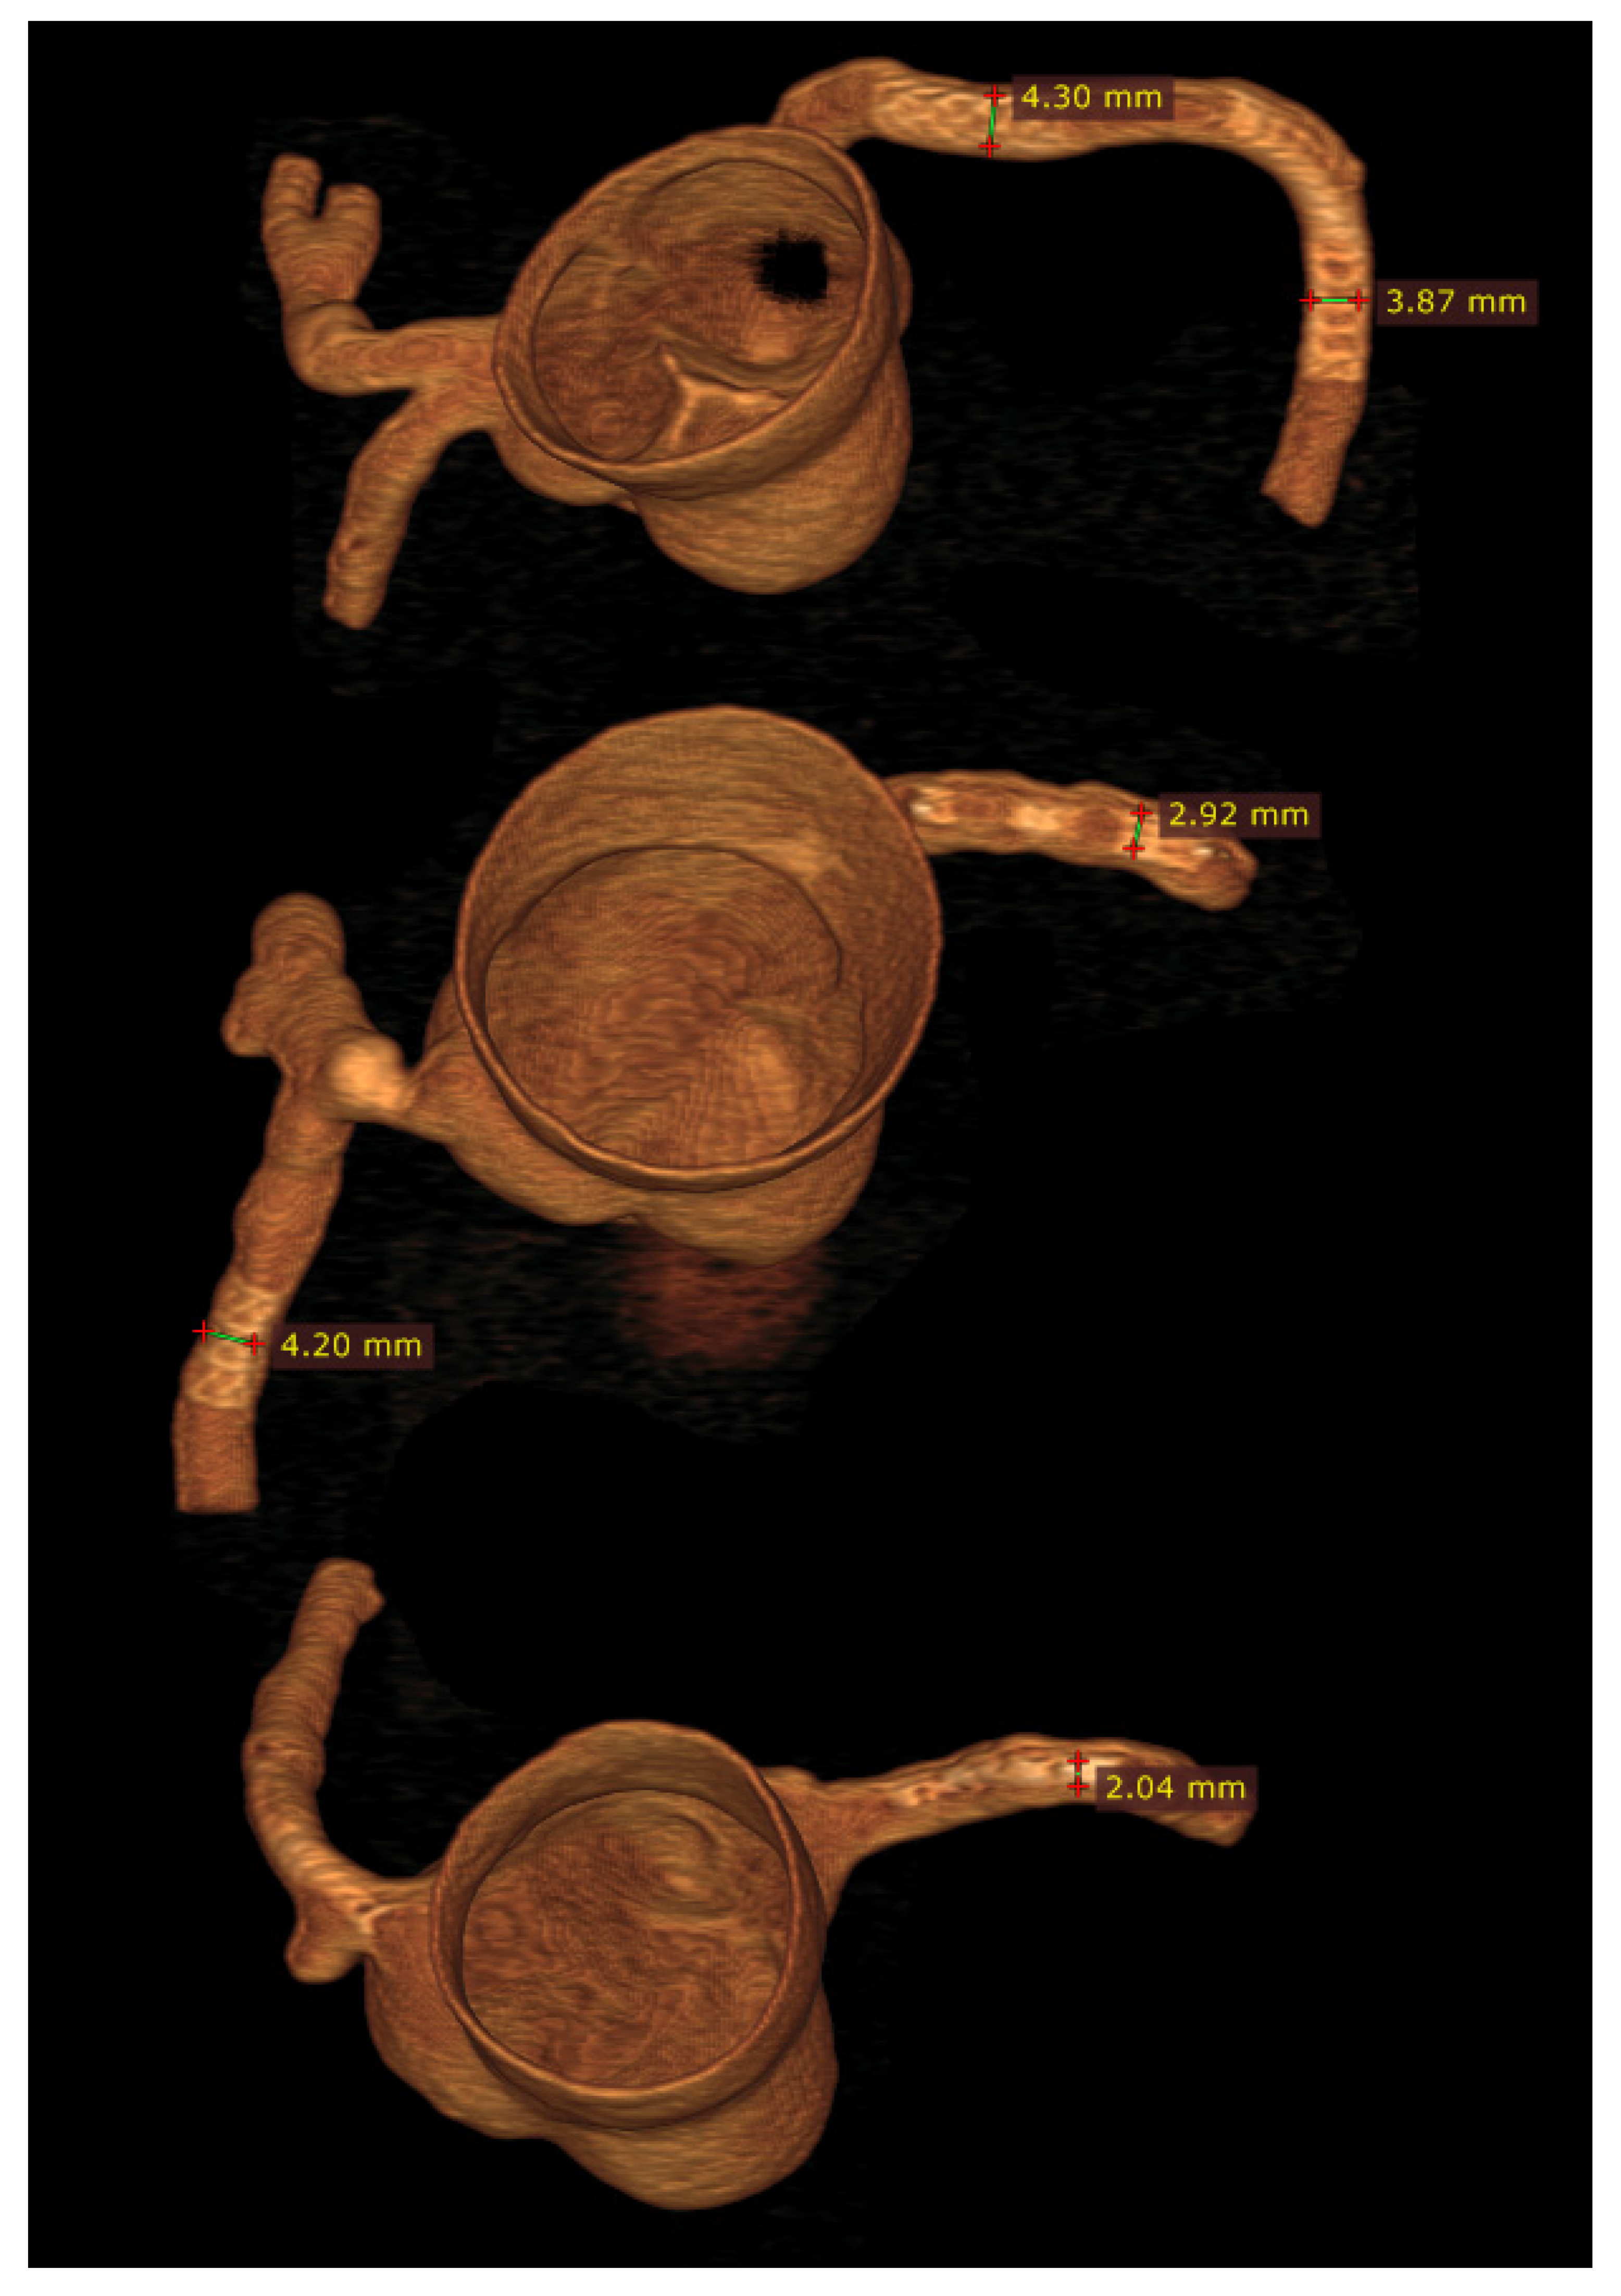

3.3. 3D Printing in Coronary Artery Disease

- Sommer, K.N.; Lyer, V.; Kumamaru, K.K.; Rava, R.A.; Ionita, C.N. Method to simulate distal flow resistance in coronary arteries in 3D printed patient specific coronary models. 3D Print. Med. 2020, 6, 19. [Google Scholar] [CrossRef] [PubMed]